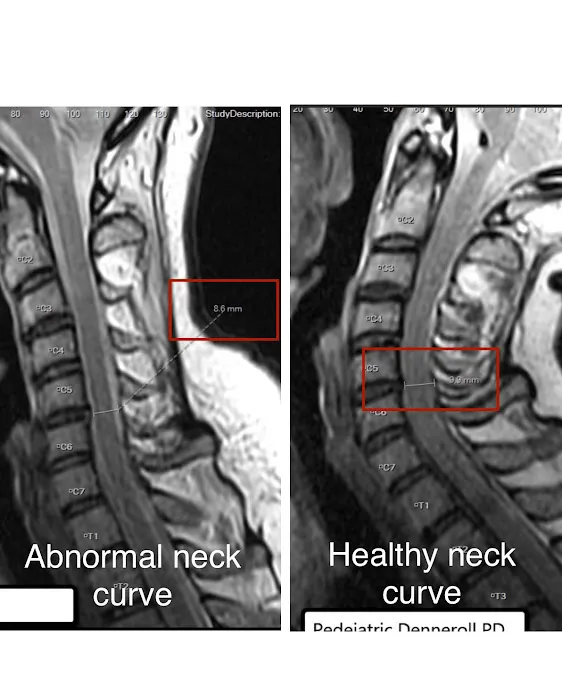

Traction Therapy: This specialized therapy is provided as part of the treatment plan. Traction helps to gently stretch the spine, decompress discs, and restore the natural curvature of the neck and low back, which is crucial for overall spinal health.

Expertise in Restoring Natural Spinal Curvature: The successful restoration of the proper curvature of the neck and low back, even amidst the physical demands of daily life, highlights Dr. Kang's specialized knowledge in structural correction.